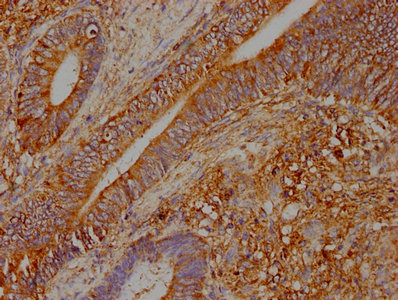

IHC image of CSB-PA025965LA01HU diluted at 1:400 and staining in paraffin-embedded human colon cancer performed on a Leica BondTM system. After dewaxing and hydration, antigen retrieval was mediated by high pressure in a citrate buffer (pH 6.0). Section was blocked with 10% normal goat serum 30min at RT. Then primary antibody (1% BSA) was incubated at 4°C overnight. The primary is detected by a biotinylated secondary antibody and visualized using an HRP conjugated SP system.

Application Recommended Dilution IHC 1:200-1:500 -